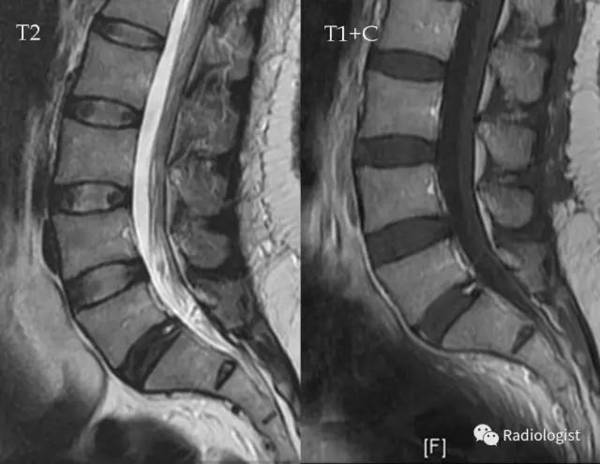

纤维环疤痕愈合图,纤维环慢慢恢复图

一个思考:如果纤维环撕裂了,含水量巨大的髓核流出来怎么办?

内窥镜辅助下腰椎髓核摘除术 纤维环缝合术

纤维环慢慢恢复图

腰椎纤维环疤痕愈合图